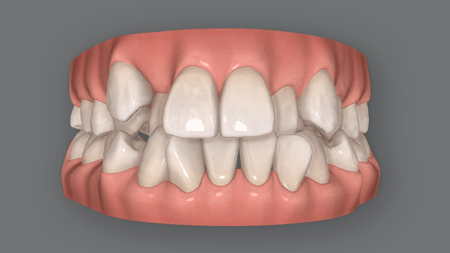

叢生(そうせい)は、ガタガタとかガチャ歯乱杭歯(らんくいば)ともいわれる、歯と歯が重なってデコボコした症状。

程度にもよりますが、不正咬合の中では最も「歯並びがガタガタしている」、そして「清潔感に欠けている」「笑顔がかわいくない」という印象のある症状です。

虫歯歯周病のリスクが非常に高い

歯が重なり合っている部分は歯ブラシの毛先が届きにくく、汚れ(歯垢)が溜まりがち。

そのため虫歯や歯肉炎、さらには歯周病へと進行するリスクが極めて高くなります。

噛み合わせがおかしくなる

叢生の原因が奥歯にある場合、特定の奥歯に過度な力が加わります。

その結果、奥歯の位置高さが変わり、噛み合わせが悪くなってしまうのです。